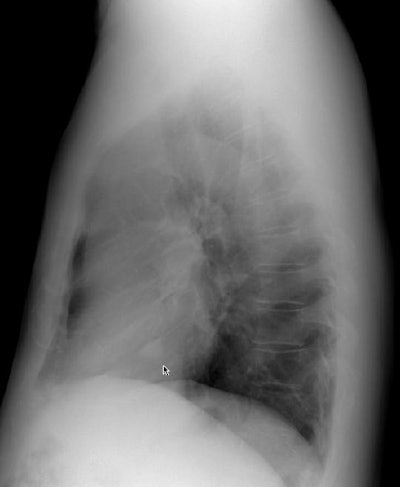

As is typical, the lesion in this case presents as a solitary pulmonary nodule within the right lower lung (it overlies the right anterior 5th rib on the PA exam, but is better seen on the lateral view). The lesion is well circumscribed and is non-calcified on computed tomography. There was no evidence of hilar or mediastinal adenopathy.